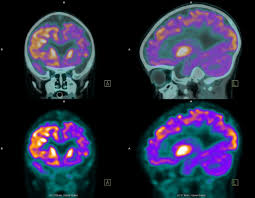

최첨단 현대의학으로 가장 적절한 방법이 양전자단층촬영술(Positron Emission Tomography, PET)이라고 나는 생각한다. PET는 체내 대사 변화를 촬영하는 기기로 CT나 MRI 다음에 개발된 영상장비이라고 한다.

요즘은 여기에 CT를 붙여서 PET 영상과 CT 영상을 융합해 서로 약점을 보완해 검사의 질을 더욱 높이고 있다고 한다.

또 부수적으로 뇌 부분의 PET 영상으로 분석해 뇌졸중, 알츠하이머 치매도 조기 진단할 수 있다고 한다. 검사도 간단해서 정맥 주사를 맞고 1시간대기 후에 20분 정도 누운 상태로 촬영한다.